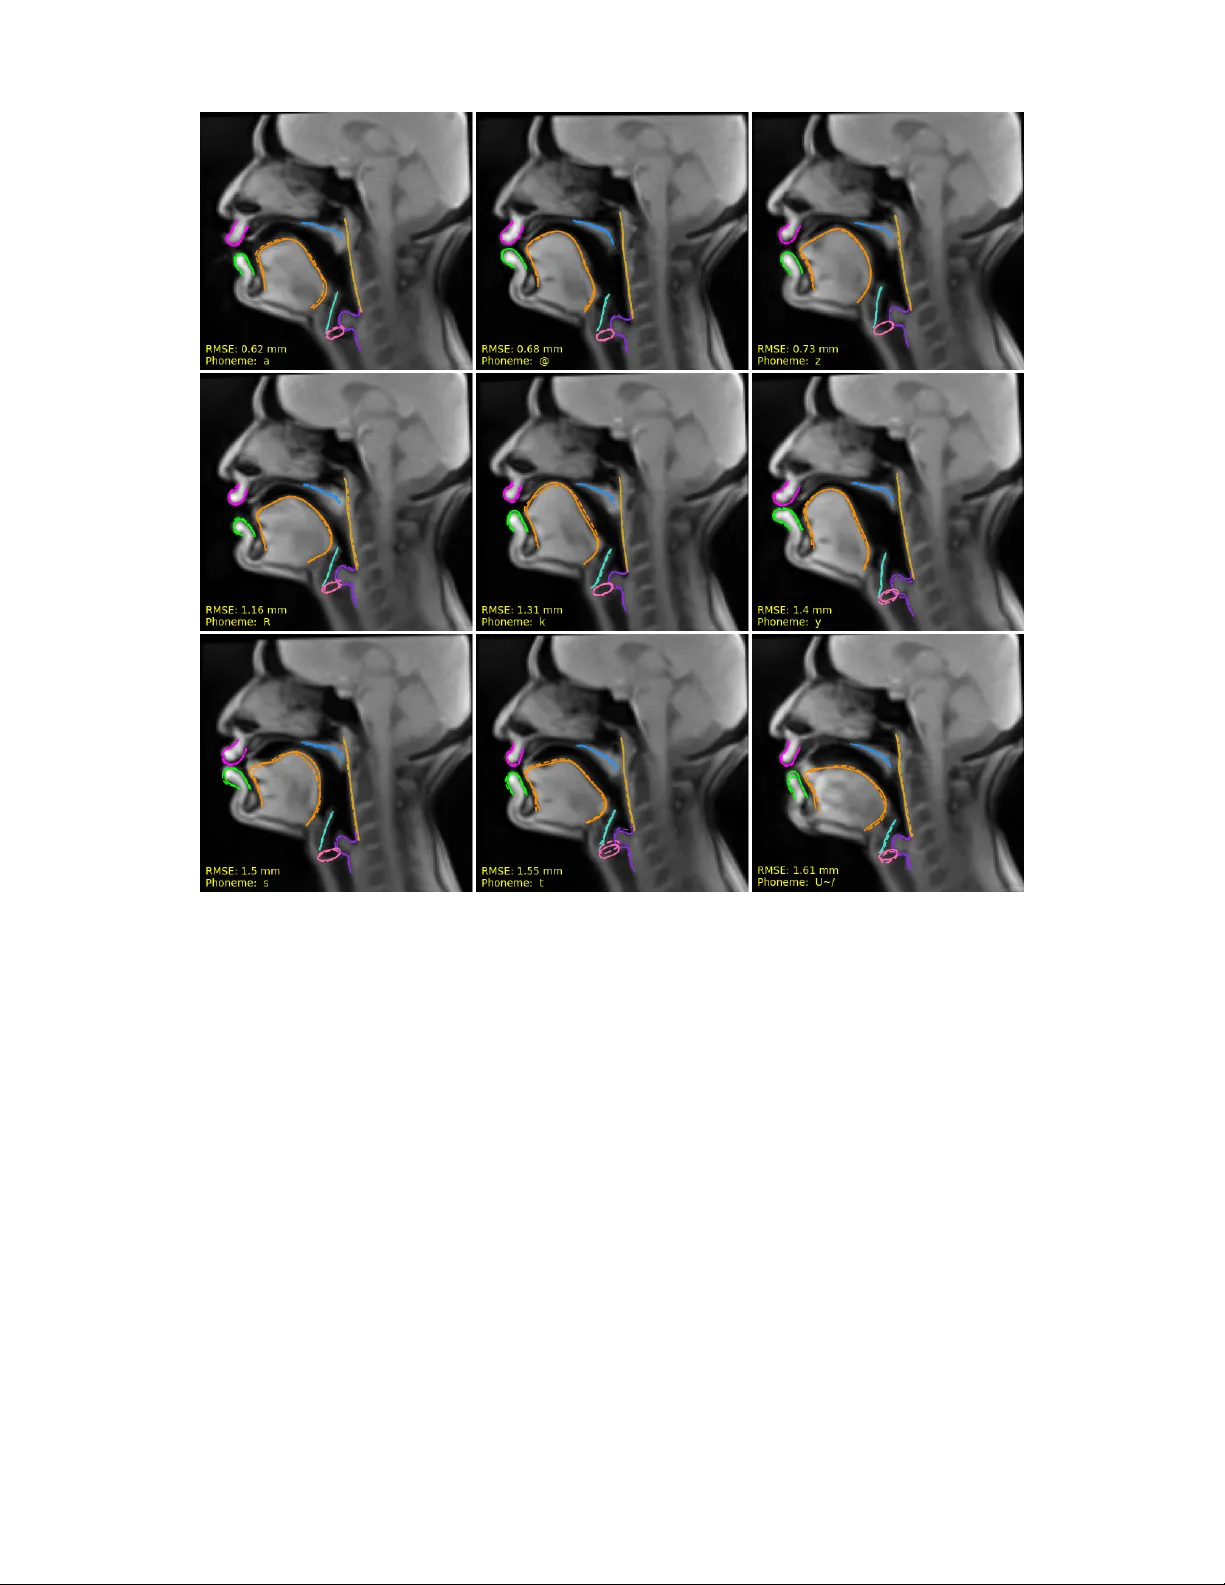

1 Acoustic-to-articulatory In v ersion of the Complete V ocal T ract from R T -MRI with V arious Audio Embeddings and Dataset Sizes Sofiane Azzouz, Pierre-Andr ´ e V uissoz, Yv es Laprie Abstract —Articulatory-to-acoustic in version str ongly depends on the type of data used. While most pre vious studies rely on EMA, which is limited by the number of sensors and restricted to accessible articulators, we propose an appr oach aiming at a complete in version of the v ocal tract, from the glottis to the lips. T o this end, we used approximately 3.5 hours of RT -MRI data fr om a single speaker . The innovation of our approach lies in the use of articulator contours automatically extracted fr om MRI images, rather than relying on the raw images themselves. By focusing on these contours, the model prioritizes the essential geometric dynamics of the vocal tract while discarding redundant pixel-level inf ormation. These contours, alongside denoised audio, were then processed using a Bi-LSTM architectur e. T wo experi- ments were conducted: (1) the analysis of the impact of the audio embedding, for which three types of embeddings were evaluated as input to the model (MFCCs, LCCs, and HuBER T), and (2) the study of the influence of the dataset size, which we varied from 10 minutes to 3.5 hours. Evaluation was performed on the test data using RMSE, median error , as well as T ract V ariables, to which we added an additional measur ement: the larynx height. The average RMSE obtained is 1.48 mm, compared with the pixel size (1.62 mm). These results confirm the feasibility of a complete vocal-tract inv ersion using RT -MRI data. Index T erms —Acoustic to articulatory in version, speech pr o- duction, rt-MRI. I . I N T RO D U C T I O N Articulatory-to-acoustic inv ersion consists in recovering the shape of the vocal tract from the speech signal. Early work on in v ersion was based on an analysis-by-synthesis paradigm. One of the first examples is W akita’ s in v erse filtering approach [1], which imposes a highly constrained model in the form of an all-pole model to enable in v ersion, with the advantage of limiting the use of articulatory data. Indeed, W akita points out that it is difficult to acquire data, that this poses risks for subjects (as the data was obtained through X-rays), and that the techniques av ailable at the time did not allow for the transverse dimension (perpendicular to the mid-sagittal plane) to be determined. The entire history of articulatory acoustic in v ersion is a kind of compromise between the complexity of an analysis model and the existence of data to adjust or replace the model. F ollo wing W akita, the analytical approach was improv ed in terms of both acoustic numerical simulations and the geometric model of the vocal tract. Recent modeling techniques are based on acoustic sim- ulations that take into account vocal folds, aerodynamics, and the acoustic properties of the vocal tract. They aim to Sofiane Azzouz and Yves Laprie are with the Univ ersit ´ e de Lorraine, CNRS, Inria, F-54000 Nancy , France (e-mail : sofiane.azzouz@loria.fr , yves.laprie@loria.fr). Pierre-Andr ´ e V uissoz is with the Uni versit ´ e de Lorraine, Inserm, IADI U1254, F-54000 Nancy , France (e-mail : pa.vuissoz@chru-nancy .fr). achiev e a formulation that is suf ficiently efficient in terms of computation time and fidelity to physics. Advances in acoustic simulations now make it possible to produce high-quality speech, as demonstrated by the V ocalT ractLab system [2]. The shape of the vocal tract and its temporal ev olution must be specified as input for these simulations. The first technique uses geometric primiti ves, cylinders whose center and radius can change, and planes in the case of a three-dimensional model [3]. This technique has the advantage of being simple, but it does not guarantee the realism of the geometric shape. A second technique consists of using medical images of the vocal tract (X-ray images in the 1970s and, since then, 2D MRI images or 3D MRI volumes), which guarantees greater realism but presents the difficulty of switching from one speaker to another . Recently , Gao and Birkholz [4] hav e used Birkholz’ s articulatory synthesizer to propose an articulatory copy synthesis system, the principle of which is to search for the parameters of the articulatory synthesis model that generate a speech signal close to the input speech. The principle is therefore very similar to articulatory acoustic in version, and the resynthesized speech appears to be of very good quality . Despite these advances, there is still a discrepancy between the underlying geometric analysis model and the actual speaker , which compromises the geometric accuracy of the inv ersion. The second approach in volves dispensing with an analysis model and establishing a direct link between the signal and the geometry of the vocal tract. W ith the advent of new techniques for acquiring articulatory data, first microbeam X- ray technology (abandoned due to the risks posed by X-rays), and especially EMA (ElectroMagnetic Articulography), it has become possible to acquire a sufficient volume of data to perform machine learning [5], [6]. Unfortunately , this data only covers a few points (3 or 4 on the tongue, 1 on the soft palate, 1 on the lower central incisor , and 2 on the lips), but it is possible to record speech for a little over 30 minutes. This technique has become widely used because, unlike the microbeam technique, it does not pose any radiological risks. On the other hand, the fact that the sensors are connected to the measuring de vice by wires slightly alters speech articulation, and these sensors often come off after about 30 minutes. The second weakness is that the articulatory information is very limited, since only the positions of seven points are known, and these points are located at the front part of the vocal tract, pro viding no information about the pharynx and larynx. Finally , if several acquisition sessions are made, it is impossible to guarantee that the sensors will be glued in the same place. In practice, e v aluations generally focus on distances between two sensors, or between a sensor and a reference contour such as the palate. 2 This data has been used for training stochastic and neural approaches. The weakness of stochastic techniques is that temporal modeling, which is essential for speech, is insuf- ficient. This explains why neural network based approaches quickly supplanted stochastic models. The architecture of neural netw orks has ev olved from multilayer networks [7] to recurrent networks, LSTMs or Bi-directional Gated Recurrent Units [8]–[10] which ha ve become the standard in recent years. Howe ver , these studies only provide partial information about the vocal tract, as they only concern the anterior part of the oral cavity , whereas it is well known that the length of the vocal tract —and therefore the position of the larynx— has a strong influence on resonance frequencies, and that there are compensation mechanisms in v olving the lower part of the vocal tract. Despite their interest in terms of taking the temporal dimension into account, the use of in version trained on EMA data is not realistic, because, from an application point of vie w , it is essential that the entire vocal tract be cov ered. Only dynamic MRI data can meet this requirement, but this necessitates high-quality data to provide reliable geometric information in suf ficient quantity [11], good spatial resolution images and high-quality denoised speech signal despite the strong noise generated by the MRI machine [12], [13]. Real- time Magnetic Resonance Imaging (rt-MRI) was introduced as an alternativ e to EMA, with the first recorded corpus described in [14]. Deep learning approaches ha v e been applied to these data [15]. Howe v er , the use of rt-MRI remains limited due to several constraints: difficulty in acquiring sufficiently large datasets, low signal quality after denoising, lack of robust contour-tracking tools, and relativ ely low spatial resolution (68x68 pixels with a voxel size of 2.9 x 2.9 x 5mm 3 or more recently 84x84 pixels with a vox el size of 2.4 × 2.4 x 6 mm 3 in [11]), along with certain MRI-related artefacts. There are two ways to perform in version. The first is implicit in v ersion, which in volv es recovering an MRI image. [15], [16] use an LSTM-based approach to recover the image, while [17] uses a diffusion model used in image synthesis. In both cases, the e v aluation is performed on the image pix els, either in terms of distance or in terms of global or local correlation. In [17] correlation focuses on a few regions of interest to the vocal tract and not the entire image. In all cases, the e v aluation does not take into account any information about the position of the articulators themselves. The first weakness is that the assessment therefore does not take into account any information relating to articulators. The second weakness is that e xploiting the inv ersion results requires a post-processing step. For example, to use the in v ersion as input for articulatory synthesis, the contours of the articulators must be extracted from the images reconstructed during the inv ersion. These images are marred by in version errors and are therefore less easy to interpret and segment automatically . The second avenue of research consists of working on the contours of the articulators, which must therefore be extracted automatically from the images. The adv antage is that the in v ersion result is directly usable since the in v ersion provides the contours of the articulators from the signal. Our work has shown that it is possible to extract the contours automatically with a high degree of reliability [18]. W e chose the second approach, which has the adv antage of pro viding information that is easy to use as articulatory feedback in educational applications or speech rehabilitation, for e xample. In our study , we used an rt-MRI dataset with good spatial resolution (136×136 pixels), good quality denoised speech signal of higher quality than most existing rt-MRI datasets. Furthermore, in contrast to previous studies that inv ert complete R T -MRI images, we opted for automatic contour tracking to extract the shapes of individual articulators, and performed in v ersion only on these contours rather than on the full image. W e use this high-quality database for both image and sound to assess the geometrical accuracy of in version. Until now , the articulatory variables used to characterize the v ocal tract from a phonetic point of view ha ve not taken into account the v ertical position of the larynx, which plays an essential role in modifying the length of the vocal tract and, consequently , its resonance frequencies. The reason for this is that it is impossible to reliably locate the position of the larynx using EMA data. As we use high-quality MRI data and contours, we hav e added this new articulatory variable to our work. W e also use a lar ge single-speak er database, which allo ws us to study in detail v arious aspects of training, such as the impact of dataset size on in version performance — using subsets of 10 minutes, 30 minutes, 1 hour, 2 hours, and the full dataset. In this paper, we propose a complete v ocal tract inv ersion approach from the glottis to the lips, striving to work under optimal conditions on a single speaker , in order to achie ve the lo west possible error rate for MRI data. Furthermore, we precisely determine the minimal amount of data required to obtain reliable and reproducible results for one speaker . I I . D A TA SE T A. corpus The corpus was recorded at the Centre Hospitalier R ´ egional de Nancy . It consists of recordings from a single female French speaker and contains 2,100 sentences, corresponding to approximately 3.5 hours of speech. The dataset is structured into 153 acquisitions, each lasting 80 seconds and containing 4,000 images acquired at a rate of 50 images per second. Each image corresponds to a 8 mm slice in the mid-sagittal plane and has a resolution of 136×136 pixels and a pixel spacing of 1.62 mm. The corresponding audio was recorded using an optical microphone at 16 kHz and then denoised with the algorithm proposed in [19]. The audio quality of denoised speech is close to clean speech (an example audio file is provided in the Supplementary Material). In addition, we also hav e precise phonetic segmentations. The AST ALI software [20] was used to perform a forced alignment, which was then carefully manually corrected by an e xpert. The corrections focused on the boundaries between sounds, most often for plosiv es. In addition, we separated the closure of voiceless plosi v es from the burst because the articulatory position changes significantly between the two parts. W e did not apply this correction to voiced plosiv es because it is often more difficult to distinguish between the two parts. 3 B. Image r e gistr ation Our data was recorded over six different sessions. In order to ensure that the speaker maintains the same posture we made a blocking foam perfectly adapted to the MRI antenna and the speaker’ s head. Despite these precautions, it is impossible for the speaker to maintain exactly the same posture during the six recording sessions and e ven during the same session, which could lead to misaligned images. T o overcome this difficulty , we realigned the images for each acquisition. A mask cov ering only the static part of the head (see Fig. 1) was created, after which rigid transformations were applied within a ±4-pixel translation range and ±4° rotation range. The transformation yielding the highest normalized cross- correlation with a reference image was then selected. Fig. 1. mask of the reference image. The green region represents the static part of the vocal tract C. Choice of input r epresentation W e explored sev eral types of speech signal modeling at the input of in version. T raditionally , MFCCs are used for in version because they have long provided the best results for automatic speech recognition [21]. One of the strengths of MFCCs is that they neutralize the influence of the fundamental frequency and attenuate dif ferences between speakers by using a non-linear frequency scale. Here, we use data from a single speaker and we thus also used linear cepstral coef ficients (LCCs) [22], which use a linear frequency scale. This should be an advantage because the formants that depend directly on the vocal tract shape are preserv ed. Self-supervised learning (SSL) models hav e recently demonstrated their ef fecti v eness in v arious speech processing tasks, particularly in articulatory acoustic in version. In [23], sev eral SSL models — such as HuBER T [24], W av2V ec2 [25], and W a vLM [26] — were compared to traditional ap- proaches based on hand-crafted acoustic features, such as Mel- frequency cepstral coef ficients (MFCCs), for the in version task on EMA data. The results showed that HuBER T outperformed all other methods. Similarly , [27] conducted experiments on XRMB data and compared the representations extracted by HuBER T to those based on MFCCs, confirming HuBER T’ s superiority through higher correlations between acoustic and articulatory signals. In this work we will therefore only com- pare the results obtained with MFCCs, LCCs, and HuBER T 1 . D. Data pr epr ocessing Unlike other works using full MRI images, the proposed method recovers the contours of articulators. The vocal tract is represented by the contours of eight articulators or cartilages: the upper lip, lower lip, tongue, soft palate midline (v elum), pharyngeal wall, epiglottis, arytenoid cartilage, and vocal folds (glottis). Additionally , two landmarks are included that do not contribute directly to the inv ersion—the lower incisor and upper incisor . Howe v er , the upper incisor is utilized in the calculation of the T ract V ariables (TVs), inspired by articulatory phonology [28]. All contours, as shown in Fig. 2, were obtained using an automatic tracking approach based on RCNN [29], dev eloped by our team. This approach, which maintains a tracking error of approximately 1.00 mm, is av ailable as open-source code 2 . Each articulator contour consists of 50 points with X and Y coordinates. The contours were normalized following the approach used in [8]. For each contour point a moving av erage was computed over the 30 preceding and following frames. This average was subtracted from the coordinates, and the result di vided by the corresponding standard de viation for each session. Three different representations were used as input features: MFCCs, LCCs, and HuBER T embeddings. The MFCCs were computed together with their first-order ( ∆ ) and second-order ( ∆∆ ) deri v ati v es, using 13 coef ficients, a windo w size of 25 ms, and a hop length of 10 ms. The LCCs were extracted using the first 30 linear cepstral coef ficients with the same window and hop sizes. F or HuBER T , we compared both the Base and Large architectures; the best results were obtained using the Base model. While the standard HuBER T was trained on English multi-speaker data, the literature indicates that the multilingual fine-tuned version, mHuBER T -147 [30], yields very similar results, what our preliminary tests hav e confirmed for inv ersion. Therefore, this study utilizes only the HuBER T -Base representation. HuBER T processes 16 kHz audio and generates 768-dimensional embeddings at a frame 1 https://huggingface.co/docs/transformers/model doc/hubert 2 https://github .com/vribeiro1/vocal- tract- se g Fig. 2. Segmentation of articulators contour tracked in two images of the rt-MRI film: Arytenoid cartilage, Epiglottis, Lo wer lip, V ocal folds, Soft palate midline, T ongue, Upper lip, Pharyngeal wall 4 rate of 50 Hz. All features (MFCCs, LCCs, and HuBER T) were normalized per session by subtracting their mean and dividing by their standard deviation. I I I . M E T H O D S A. Model ar chitectur e Our model is based on a bidirectional LSTM (Bi-LSTM) architecture [31], [32], which has demonstrated strong per- formance for this specific task. The choice of a Bi-LSTM is motiv ated by its inherent ability to capture bidirectional temporal dependencies, which are crucial for modeling the anticipatory and carryov er coarticulation effects [33] in speech production. The architecture consists of fi ve layers and takes acoustic feature vectors as input, passes through two dense layers with 300 units each, followed by two bidirectional LSTM layers, each consisting of 300 units (see Fig. 3). The output is generated by a dense layer , producing a tensor of size 100 × 8 (number of articulators), where 100 represents the contour coordinates (50 for the X coordinates and 50 for the Y coordinates). In our previous work [32], we tested sev eral v ariants of this model, including an 8-layer version, and we concluded that this model is sufficient to perform this task. B. Loss function Since acoustic-to-articulatory in version is a regression task, the Mean Squared Error (MSE) is the most commonly used loss function. MSE = 1 n n X i =1 ( y i − ˆ y i ) 2 (1) where n represents the total number of the contour points, y i and ˆ y i represent the true and predicted v alues of the output for example i , respectively . W e use the sum of the Mean Squared Error for all the contours of each frame to minimize the distance between the predicted and the ground-truth articulatory positions. C. Evaluation First, the data were denormalized by multiplying with the standard deviation and adding the mean used to normalize each articulator . we ev aluated the model using the average RMSE. For each image, we computed the mean RMSE for each articulator, by considering its 100 coordinates. Then, we calculated the mean error across all articulators, which giv es us the image-level RMSE. After obtaining the RMSE for each image, we computed the median as well as the overall mean RMSE across all images. These values are expressed in millimeters (mm). RMSE = v u u t 1 n n X i =1 ( y i − ˆ y i ) 2 (2) I V . A RT I C U L ATO RY T R A J E C T O R I E S The acoustic impact of a geometric error depends on the distance between the two walls of the vocal tract, usually a fixed wall, such as the palate, and a mobile articulator , such as the tongue. The smaller this distance, and therefore the greater the constriction, the greater the acoustic impact, which determines the realization of a phonetic feature. An articulator is critical for a phoneme if it corresponds to a minimum distance, i.e. a constriction, and the tract variables (VT) of articulatory phonology [28] correspond to the points or regions of the vocal tract that play a critical phonetic role for one or more phonemes. Unlike global metrics such as RMSE applied to articulatory contours, TVs thus allow for targeted e v aluation of the articulatory gestures specific to each phoneme. These distances provide a more functionally meaningful assessment Fig. 3. Architecture of the model 5 of articulatory in v ersion quality , as they reflect constrictions formed in the vocal tract and the y are directly linked to con- striction re gions in the vocal tract. They were defined within the framework of gestural phonology , sho wn in the Fig. 4, and the tract variables with their corresponding constrictors are presented in T able I. Unlike EMA data, we do not have fixed points directly located on the critical articulators required for computing the TVs. In our case, for each TV , we selected a set of points on the two articulators in order to approximate as closely as possible the anatomical reference points. W e ha ve added the larynx height (see Fig. 4 and subsec- tion IV -B) as a ne w variable that we believe to be important. It does not correspond to a constriction, b ut has a significant acoustic impact on resonance frequencies. A. V elum movement The velum is elongated in shape, and we chose to use its midline because it of fers greater robustness in terms of tracking and modeling. The main mov ement of the velum corresponds to an opening/closing that allows or prevents airflow into the nasal cavities. An initial idea is to measure the distance between the lower end of the midline, i.e. the velum tip, and the pharyngeal wall, but this has two weaknesses. The first is that the distance between this point and the pharyngeal wall is never zero since it is in the middle of the Fig. 4. V isual Representation of the V arious V ocal Tract V ariables (TVs) represented by dashed lines : LP , LA, LD, TTCD, TBCD, TRCL, TRCD, LH velum and therefore does not contact this wall. The second weakness is that the velum thickness is minimal at this point, which reduces the image contrast and consequently reduces the robustness of the tracking. T o estimate the dynamics of velum opening and closing we thus characterize velopharyngeal mov ement more com- prehensiv ely by defining a subset of 25 points along the midline, starting at the velum tip and extending posteriorly (see Fig. 5). This re gion was chosen because it corresponds anatomically to the portion of the v elum most directly in v olved in the velopharyngeal closure gesture, thereby providing a detailed representation of its motion during both lowering (opening) and raising (closing) phases. A principal component analysis (PCA) was applied to these 25 midline points across the entire dataset including all silences, with all articulatory coordinates centered and normalized prior to analysis to ensure that differences in absolute position do not bias the results. Similarly to [34] the first principal component PC1, which accounted for 57% of the total v ariance in our dataset (59% in [34]), was interpreted as representing the primary degree of freedom corresponding to the opening/closing gesture of the velum. For each frame in the dataset, the degree of velum opening or closure was quantified by projecting the 25-point midline configuration onto PC1. This projection, i.e. the dot prod- uct between the PC1 loading vector and the current velum configuration, yielded a scalar score that we term the PC1 score. The polarity of PC1 was defined such that positiv e scores indicate motion in the opening direction (velopharyn- geal port enlar ging), whereas negativ e scores indicate motion in the closing direction (velopharyngeal port constricting). Thus, in the context of our analysis, large positi ve PC1 scores correspond to maximal opening, large ne gati ve scores to maximal closure, and values near zero to intermediate or neutral positions (see Fig. 5). By reducing the velopharyngeal movement to this single physiologically interpretable dimension, we were able to track the temporal evolution of the gesture with high precision. B. Larynx height In addition to the vocal tract variables (TVs) already studied in the literature [28], we introduced a new metric that consists of measuring the larynx height. T ABLE I V O C A L T R AC T V AR I A B LE S A ND T H EI R A SS O C I A T E D C O N S TR I C TO R D I S T A N CE S . VT V ariable Definition / Distance LA Lip Aperture V ertical distance between the upper and lower lips (mouth opening) LP Lip Protrusion Forward displacement of the lips along the anterior-posterior axis LD Lip Constriction Degree Distance between the lower lip and the upper teeth TTCD T ongue T ip–Palate Distance Distance between the tongue tip and the hard palate TBCD T ongue Body–Palate Distance Distance between the tongue body and the hard palate TRCD T ongue Root Constriction Degree Distance between the tongue root and the posterior pharyngeal wall TRCL T ongue Root Constriction Location Position along the vocal tract where the tongue root occurs VEL V elic Opening Distance Distance between the velum and the posterior pharyngeal wall LH Larynx height V ertical distance between the glottis and the hard palate 6 Fig. 5. Example of two velopharyngeal port opening configurations: open (4.69) and closed (–9.68). Original points, Projected points. It is defined as the distance from the glottis to the hard palate right extremity (see Fig. 6), used as the reference. This measurement is particularly important for character- izing the vertical dimensions of the vocal tract, which hav e a direct influence on the resonance frequencies of the vocal tract. T o perform this calculation, we first defined the center of the glottis as the geometric centroid of its contour points. The distance was then measured from this center to a specific reference point on the hard palate (see Fig. 6), ensuring that this measurement was taken along an axis parallel to the pharyngeal wall. This orientation guarantees anatomical relev ance and provides better consistency with the vocal tract structures. T o our knowledge, previous studies ha ve nev er succeeded in measuring this specific v ariable of the vocal tract directly inside the vocal tract due to the limitations of electromagnetic articulography (EMA), which makes it impossible to position a sensor at the lev el of the larynx. The only option w as to deduce the position of the larynx from video images of the speaker’ s head [35], which necessarily introduces a high degree of inaccuracy . Furthermore, on the MR imaging side sev eral technical challenges have pre vented this analysis: either the anatomical contours were not segmented accurately , or the anatomical structures were not suf ficiently visible due to insufficient image resolution. Introducing this ne w vocal tract v ariable is a major advan- tage, since it provides a better understanding of the impact of v ocal tract dimensions on the acoustic characteristics of speech, particularly on vocal resonances, or formants, which are fundamental for v o wel perception and identification. C. Calcul of TVs Unlike EMA data, which consist of discrete sensor points, our data comprise full articulatory contours. Before computing the tract variables, all contours were first denormalized. T o estimate the relev ant distances, we selected a specific range of points on each articulator and calculated the minimum Eu- clidean distance between these regions. This approach allo ws us to approximate constriction locations without relying on individual point measurements. Distances were computed for each tract variable (TV) and each frame independently , for both the original and predicted contours. Fig. 6. V isual Representation of the Larynx height LH Upper incisor with hard palate The Pearson correlation, as shown in ( 3), was then used to quantify the relationship between each TV extracted from the original contours and those derived from the predicted contours, for all TVs. Pearson = P n i =1 ( x i − ¯ x )( y i − ¯ y ) p P n i =1 ( x i − ¯ x ) 2 , p P n i =1 ( y i − ¯ y ) 2 (3) For velum mov ement, in addition to the Pearson correlation, we also used another metric. Since we consider any positive value as open and an y negati v e v alue as closed, we represented these states as 1 and –1, respectively . T o ev aluate the agree- ment between the original and predicted TVs in this case, we used accuracy , as defined in ( 4): Accuracy = Number of correct predictions T otal number of predictions (4) Accuracy provided better results than the Pearson correla- tion, which is why we decided to keep and report only the accuracy scores. D. Experiments Our primary objective is to successfully perform the in- version of the complete v ocal tract contour under the best possible conditions. T o this end, we conducted two distinct experiments. The first experiment aimed to e v aluate the impact of different acoustic input representations on the model’ s performance. Three types of inputs were considered. First, the Mel-Frequency Cepstral Coefficients (MFCCs), which are widely used in articulatory in version studies and generally yield e xcellent results. Second, LCCs, which pro vide higher - quality acoustic information. Indeed, some spectral peaks can be attenuated in MFCCs due to Mel-scale filtering and compression. LCCs, being more directly related to the spectral en v elope of the vocal tract, enable the model —particularly in a single-speaker scenario— to establish a more direct mapping between acoustic features and articulatory trajectories. Finally , we ev aluated a self-supervised learning (SSL) embedding obtained from the HuBER T model, which has demonstrated promising results in pre vious studies [27], even outperform- ing MFCC-based representations. T rained to predict masked 7 acoustic representations, HuBER T produces rich and contex- tual embeddings capable of capturing fine-grained temporal and spectral information, making it particularly well-suited for complex tasks such as acoustic-to-articulatory inv ersion. The second experiment focused on in v estigating the influ- ence of dataset size on model performance. W e examined whether similar results could be achie ved using smaller subsets of datasets. T o this end, the model was trained on datasets of increasing duration: the full 3.5-hour corpus, 2 hours, 1 hour, 30 minutes, and 10 minutes. In this experiment, the LCCs features were used as the model input and ev aluations were conducted against the same complete test set. E. Model par ameters All models were trained for 300 epochs with a batch size of 10, using the Adam optimizer with an initial learning rate of 0.001. T o av oid overfitting early stopping w as applied with a patience of 10 epochs on the validation data, halting training if no improv ement was observed. Our dataset contains 450,000 images after removing silence.W e randomly di vided our dataset by acquisitions into 80% for training, 10% for validation, and 10% for testing. All experiments were run with the same training configura- tion and train-validation-test splits to ensure a fair comparison. The entire implementation was done using PyT orch. F . Statistical Significance of the Results T o ev aluate whether the performance dif ference between different results is statistically significant, we accounted for the temporal dependency inherent in consecuti v e frames. The original test set contained 45,000 frames; ho wever , consecutiv e frames are highly correlated. T o ensure the independence of observations required for statistical testing, we aggre gated the results by calculating the mean score for consecutiv e frames within the same phone. This process resulted in a reduced but more robust sample of n = 10 , 871 independent observations. Since the distribution is not normal (as tested with the D’Agostino test), the W ilcoxon Signed-Rank T est was used with a significance threshold of α = 0 . 05 . V . R E S U LT S First, we verified that our model does not o verfit. For instance, the LCC-based model achiev ed an error of 1.48 mm on the test set, which is lower than the validation error of 1.63 mm. This slightly superior performance on the test set suggests that the model did not overfit. All training runs con verged in fewer than 150 epochs for both experiments, and all reported differences were tested for statistical significance using Wilcoxon test to ensure that the observed performance variations between embeddings and dataset sizes were meaningful. The first experiment compared the model’ s performance when trained with three different types of acoustic embed- dings: MFCCs, LCCs, and HuBER T . As sho wn in T able II, LCC-based model achieved the best ov erall performance across all articulators, with an average RMSE of 1.48 mm and a median error of 1.27 mm, follo wed by HuBER T -based model (RMSE = 1.49 mm, median = 1.31 mm) and MFCC- based model (RMSE = 1.51 mm, median = 1.30 mm). When examining each articulator indi vidually , LCC-based model outperformed the other embeddings for six articulators and tied with HuBER T -based model for one — the epiglottis — where both reached an RMSE of 1.49 mm and a median of 1.31 mm. HuBER T -based model slightly surpassed LCC-based model for the tongue, with RMSE and median values of 2.20 mm and 1.99 mm, compared to 2.28 mm and 2.04 mm for LCC-based model. Ov erall, MFCC-based model consistently yielded the lowest performance across all articulators. Fig. 7 shows a boxplot for the LCC-based model, illustrating the v ariability of the mean RMSE for each frame. It also indicates the distribution of outliers. Fig. 8 presents the Pearson correlations between ground- truth and predicted articulatory variables. HuBER T -based model achieved the highest correlations for most variables, ex- cept for LD, where it tied with LCC-based model (correlation = 0.91). Overall, HuBER T -based model’ s correlations ranged from 0.88 to 0.92, followed by LCC-based model (0.86–0.91) and MFCC-based model (0.84–0.91). Fig. 10 shows examples of predicted and ground-truth contours using LCC-based model as input, with mean RMSE T ABLE II C O MPA R IS O N O F R MS E ( MM ) A ND M E DI A N E R RO R ( MM ) F OR D I FFE R E NT I N PU T F EAT UR E S : M F C C S , L CC S , A N D H U B E R T E M B E DD I N G S . MFCC-based model HuBER T -based model LCC-based model Articulator RMSE Median RMSE Median RMSE Median Arytenoid 1.63 ∗ ± 1.02 1.38 1.63 ± 1.00 1.39 1.60 ± 1.00 1.35 Epiglottis 1.52 ∗ ± 0.88 1.33 1.49 ∗ ± 0.84 1.31 1.49 ± 0.85 1.31 Lower lip 1.53 ∗ ± 0.83 1.35 1.48 ± 0.80 1.31 1.47 ± 0.81 1.30 Pharyngeal 1.08 ± 0.58 0.96 1.09 ± 0.56 0.98 1.07 ± 0.57 0.94 V elum 1.34 ± 0.67 1.21 1.35 ± 0.65 1.23 1.33 ± 0.66 1.20 T ongue 2.33 ∗ ± 1.17 2.10 2.20 ∗ ± 1.12 1.99 2.28 ± 1.14 2.04 Upper lip 1.15 ∗ ± 0.55 1.03 1.20 ∗ ± 0.58 1.09 1.11 ± 0.53 1.01 V ocal folds 1.49 ∗ ± 0.84 1.31 1.47 ∗ ± 0.76 1.33 1.46 ± 0.80 1.30 Mean 1.51 ∗ ± 0.91 1.30 1.49 ∗ ± 0.87 1.31 1.48 ± 0.89 1.27 ∗ Significant dif ference compared to the LCC-based model result ( p < 0 . 05 ) based on a W ilcoxon test. 8 Fig. 7. Boxplot of mean RMSE per frame for the LCC-based model, showing outlier ranges. The red curve shows the distribution of # outliers. The right axis gives the number of outliers as a function of the error in mm. values ranging from 0.62 mm to 1.61 mm. The second experiment ev aluated the impact of dataset size on model performance using LCC-based model as input. Fig. 9 shows the decrease in the mean RMSE from 1.75 mm to 1.48 mm, the mean median from 1.51 mm to 1.27 mm, as well as the tongue RMSE from 2.78 mm to 2.28 mm as the amount of training data increases from 10 minutes to 3.5 hours. T able III further indicates that, when examining indi vidual articulators, the 3.5-hour dataset produced the lo west RMSE and median values. Performance followed a clear hierarchical trend, with errors increasing as dataset size decreased from 2 hours to 1 hour , 30 minutes, and finally 10 minutes, which yielded the highest errors overall. V I . D I S C U S S I O N A. Comparative Analysis of Input F eatures T able II presents the results of the first experiment, which aims to compare different acoustic representations used as model inputs: MFCCs, LCCs, and HuBER T embeddings. The results sho w that LCC-based model provide the best performance, both globally (a v eraged over all articulators) and individually , except for the tongue, where HuBER T -based model achieves slightly better results. HuBER T -based model ranks second, while MFCC-based model yield the lowest performance. These results and their ranking can be explained by the specific nature of the information captured by each type of representation. LCCs are computed directly from the linear spectrum of the signal, without relying on the Mel scale, which is perceptually based. In the context of a single speaker , this spectral richness allows the model to learn a more direct mapping between acoustic features, especially spectral prominences corresponding to resonance frequencies, and articulatory trajectories. Indeed, for a given resonance cavity , the resonance frequencies are ev enly spaced, so it is Fig. 8. Correlation between the predicted and target trajectories for each measured tract variable. 9 T ABLE III C O MPA R IS O N O F R MS E ( MM ) A ND M E DI A N ( M M ) B Y VARY I N G T H E S I ZE O F T H E D A TA S ET . 10 minutes 30 minutes 1 hour 2 hours 3.5 hours Articulator RMSE Median RMSE Median RMSE Median RMSE Median RMSE Median Arytenoid 1,82 ∗ ± 1.07 1,57 1.73 ∗ ± 1.03 1.48 1.70 ∗ ± 1.01 1.45 1.65 ∗ ± 1.01 1.41 1.60 ± 1.00 1.35 Epiglottis 1.81 ∗ ± 1.00 1.61 1.67 ∗ ± 0.93 1.48 1.61 ∗ ± 0.92 1.41 1.57 ∗ ± 0.88 1.38 1.49 ± 0.85 1.31 Lower lip 1.83 ∗ ± 0.99 1.61 1.78 ∗ ± 0.97 1.57 1.59 ∗ ± 0.86 1.40 1.52 ∗ ± 0.83 1.34 1.47 ± 0.81 1.30 pharyngeal 1.22 ∗ ± 0.66 1.08 1.15 ∗ ± 0.61 1.03 1.16 ∗ ± 0.61 1.04 1.10 ∗ ± 0.58 0.98 1.07 ± 0.57 0.94 V elum 1.55 ∗ ± 0.77 1,40 1.52 ∗ ± 0.72 1.39 1.43 ∗ ± 0.71 1.29 1.37 ∗ ± 0.68 1.24 1.33 ± 0.66 1.20 T ongue 2.78 ∗ ± 1.36 2.50 2.60 ∗ ± 1.27 2.33 2.48 ∗ ± 1.24 2.22 2.37 ∗ ± 1.20 2.11 2.28 ± 1.14 2.04 Upper lip 1.27 ∗ ± 0.60 1.15 1.21 ∗ ± 0.57 1.10 1.19 ∗ ± 0.56 1.08 1.16 ∗ ± 0.56 1.04 1.11 ± 0.53 1.01 V ocal folds 1,72 ∗ ± 0.95 1.52 1.62 ∗ ± 0.88 1.43 1.58 ∗ ± 0.86 1.40 1.52 ∗ ± 0.82 1.34 1.46 ± 0.80 1.30 Mean 1,75 ∗ ± 1,05 1.51 1.66 ∗ ± 0.99 1.43 1.59 ∗ ± 0.95 1.37 1.53 ∗ ± 0.92 1.32 1.48 ± 0.89 1.27 ∗ Significant dif ference compared to the 3.5 hours dataset result ( p < 0 . 05 ) based on a Wilcoxon test. Fig. 9. Comparison of tongue RMSE, mean RMSE, and median error by varying the dataset size. normal that LCCs corresponding to a linear frequency scale giv e better results. In other words, LCCs establish a more linear and physically interpretable relationship between the acoustic signal and the vocal tract geometry . Howe v er , this gain in robustness for a single speaker would disappear if multiple speakers had to be taken into account. HuBER T embeddings, deriv ed from self-supervised learn- ing, encode rich and conte xtual representations of the speech signal. By being trained to predict masked acoustic segments, HuBER T captures temporal dependencies and preserves fine acoustic variations that are directly related to articulatory con- figurations. Thus, although the results obtained with HuBER T - based model are highly satisf actory , they remain slightly belo w those of cepstral coefficients for the specific task of acoustic- to-articulatory in version. Finally , MFCCs—although widely used in speech process- ing—are based on a perceptual frequency scale (the Mel scale) and logarithmic compression. This design, oriented tow ard human auditory perception rather than the physical production of speech, attenuates high-frequency components that contain essential cues for accurately reconstructing articulatory move- ments. As a result, MFCC-based model show lower in v ersion accuracy compared to the other representations. According to Fig. 8, strong correlations are observed, ex- ceeding 84% for all tract v ariables. Among the three types of acoustic representations, HuBER T -based model consistently outperforms the others, achie ving the highest correlations across all variables. This superiority can be explained by the fact that, although it shows slightly higher RMSE and median values compared to LCC-based model, HuBER T -based model is able to accurately predict the contours of the articulators most in volv ed in the production of the tar get phoneme. Howe ver , it sometimes produces larger errors for articula- tors that are less in v olved in the same sound, as discussed in subsection VI-B. This behavior is consistent with the nature of the model: HuBER T , based on self-supervised learning, extracts conte xtual and phonetically rich representations, while LCC-based model, grounded in a physical and deterministic modeling of the acoustic signal, maintain a more direct cor - respondence with articulatory reality . Regarding MFCC-based model, although they show solid performance, their correlations remain slightly lower than those obtained with LCC-based model and HuBER T -based model. They effecti vely capture low-le v el acoustic properties through Mel-scale filtering and logarithmic compression, but their representational capacity remains limited for modeling articulatory dynamics and coarticulation effects. It is not possible to compare our results with those in the literature because we hav e complete contours, whereas others only use information from a fe w points. Howe v er , regarding the correlation of articulatory variables, we obtain an ov erall correlation of 90%, compared to 81% in the case of [27]. T ABLE IV N U MB E R O F O UT L I E RS B Y T Y P E Outlier type # Image ambiguity 7 Global shift 8 T racking error 2 Critical articulator correct 29 In version error 54 10 Fig. 10. Illustration of inference images. The dotted lines represent the predicted values, while the solid lines correspond to the ground truth. B. Outliers During our tests, we did not limit ourselves to ev aluating the global average RMSE; we also examined the mean RMSE for each frame indi vidually (see Fig. 7). This analysis revealed that, for certain frames, the av erage RMSE reached very high values—exceeding 6 mm—compared to the global averages of 1.48 mm for LCC- based model T o identify these outliers, we computed the standard deviation (STD) and considered any value above the third quartile (Q3) as an outlier . W e examined the 100 images with the most significant in v ersion outliers to better understand the origin of these errors. This in vestigation revealed fi ve categories of outliers, summarized in T able IV, with the number of images corre- sponding to each category . Fig. 11 provides an illustration of each category . The fiv e categories are: 1) Images that are ambiguous due to MRI technical con- straints during acquisition [12]. It is impossible to deter- mine the contours and therefore to ev aluate the in version. 2) All articulator contours are shifted. The speaker’ s posi- tion has changed slightly , resulting in a slight translation of the position of all their articulators. The in v ersion therefore generates contours that are all shifted, leading to a significant outlier ev en though the overall shape of the vocal tract is correct. 3) The position of the critical articulator is correct, but the positions of the other articulators are incorrect. This concerns almost exclusi v ely stops and the uvular consonant / K /. 4) The contours produced by automatic tracking are incor- rect, and the result of the in version is closer to the actual shape of the v ocal tract. 5) The in version is incorrect, and one or more articulators are not in the expected position. This analysis shows that inv ersion errors account for just ov er half of the outliers. Cate gories 1 to 3 correspond to the process of forming the MRI images themselves, automatic contour tracking, or a small change in the speaker’ s posture. These three cate gories account for 17% of the outliers. Cate- gory 4 is interesting because the critical articulator is correctly 11 Fig. 11. Illustration of each of the 5 types of outliers. From top to bottom and left to right: image ambiguity (tongue), global shift, tracking error (tongue), correct critical articulator (correct lip position), in version error (tongue) in v erted. It accounts for 29% of cases. This mainly concerns plosiv es and, in some cases, nasal vo wels. For /p/, for example (Fig. 11) (first image of the second row), the position of the lips is correct, but that of the other articulators is not. In this case, only the position of the lips is decisiv e, and the speaker can anticipate the position of the other articulators to minimize their articulatory effort. The last category is that of in v ersion errors. The position of one or more articulators is incorrect. For vo wels, it is possible to achie ve the same target in terms of formants with different shapes, e ven if this articulatory variability depends on the vowels [36], but we did not use acoustic simulation to verify that the in verted shapes could giv e the same acoustic parameters because, from a phonetic point of view , they seem very far from the expected result. In summary , it is interesting to note that almost half of the outliers can be explained by problems other than the in version process itself. C. Impact of Dataset Size on Model P erformance The results of the second experiment indicate that the 3.5- hour dataset produced the best overall performance for all articulators. Both the root mean square error (RMSE) and median error increase monotonically as the training duration decreases, with accuracy declining substantially for datasets smaller than 1 hour . Notably , the mar gin of impro vement diminishes as the dataset gro ws; for instance, the difference in RMSE between the 10-minute and 30-minute subsets was 0 . 09 mm, whereas the difference between the 3.5-hour and 2-hour datasets was only 0 . 05 mm. This suggests that while increasing data volume consistently reduces error , performance has not yet stabilized, implying that even larger datasets may be required for full model con v ergence. Interestingly , the 1- hour subset achie v ed an average RMSE of 1 . 59 mm—which is on the same order of magnitude as the pixel size ( 1 . 62 mm)—indicating that the model performs reasonably well ev en with a moderately sized dataset. This highlights the model’ s robustness and suggests that a 1-hour dataset may be sufficient for practical applications where data collection is costly or difficult to achieve. V I I . C O N C L U S I O N T o our knowledge, this is the first study to achieve an RMSE of 1.48 mm and a median error of 1.27 mm across all vocal-tract articulators — from the glottis to the lips — using R T -MRI images. In comparison, our previous work [32] reported 1.65 mm and 1.47 mm, respectiv ely . These findings demonstrate the feasibility of performing a complete vocal- tract in version from R T -MRI data. W e also analyzed the articulatory v ariables for which HuBER T -based model achiev ed the highest correlation scores, all exceeding 88%, demonstrating its strong capacity to model articulatory dynamics. In particular , the Larynx Height (LH) variable provides new insights into characterizing the vertical dimensions of the vocal tract, which have often been over - looked in prior studies. In terms of dataset size, to our knowledge, this is the largest R T -MRI corpus available for a single speaker , compared to those reported in the literature. This allo wed us to conclude that our model trained with one hour of speech produced very satisfactory results, with only a very slight decrease in performance compared to three hours of data, i.e., 0.03 mm in RMSE. 12 In addition, we ev aluated the robustness of the model by testing it on speech recorded in a clean en vironment [37], following a training phase conducted exclusiv ely on denoised speech. This study confirms the model’ s ability to adapt to changes in the acoustic characteristics of the input signal. It is worth noting that the model was trained exclusiv ely on a single speaker , which may limit its generalization to unseen speakers. Future work will focus on developing a speaker- independent model, where the potential of HuBER T -based model representations could be further demonstrated. Beyond its theoretical significance in speech science, acous- tics to articulatory inv ersion holds great potential for practical applications in speech synthesis, automatic speech recognition, clinical phonetics, and silent speech interfaces. This study aims to establish a robust and bidirectional link between articulatory gestures and their acoustic manifestations. Furthermore, it seeks to characterize the specific role of each articulator, providing insights that could help compensate for potential perturbations affecting individual articulatory mechanisms. R E F E R E N C E S [1] H. W akita, “Direct estimation of the vocal tract shape by in verse filtering of acoustic speech waveforms, ” IEEE Tr ansactions on Audio and Electroacoustics , vol. 21, no. 5, pp. 417–427, 1973. [2] P . Birkholz, “Modeling consonant-vo wel coarticulation for articulatory speech synthesis, ” PLOS one , vol. 8, no. 4, 2013. [3] P . Birkholz and D. Jackel, “ A three-dimensional model of the v ocal tract for speech synthesis, ” in 15th International Congr ess of Phonetic Sciences - ICPhS’2003, Barcelona, Spain , Aug 2003, pp. 2597–2600. [4] Y . Gao, P . Birkholz, and Y . Li, “ Articulatory copy synthesis based on the speech synthesizer vocaltractlab and conv olutional recurrent neural networks, ” IEEE/ACM T ransactions on A udio, Speech, and Langua ge Pr ocessing , vol. 32, pp. 1845–1858, 2024. [5] A. Wrench and W . Hardcastle, “ A multichannel articulatory database and its application for automatic speech recognition, ” in Proceedings of the 5th Seminar on Speech Production: Models and Data , 01 2000. [6] K. Richmond, P . Hoole, and S. King, “ Announcing the electromagnetic articulography (day 1) subset of the mngu0 articulatory corpus, ” in Pr oceedings of the 12th Interspeec h Conference , 08 2011, pp. 1505– 1508. [7] K. Richmond, “ A trajectory mixture density network for the acoustic- articulatory in version mapping, ” in Proceedings of the Annual Confer- ence of the International Speech Communication Association, INTER- SPEECH , vol. 2, 09 2006. [8] M. Parrot, J. Millet, and E. Dunbar , “Independent and Automatic Evaluation of Speaker-Independent Acoustic-to-Articulatory Reconstruction, ” in Pr oceedings of INTERSPEECH 2020, 21st Annual Confer ence of the International Speech Communication Association , ser . Proceedings of INTERSPEECH 2020, 21st Annual Conference of the International Speech Communication Association, Shanghai / V irtual, China, Oct. 2020, pp. 3740–3744. [Online]. A v ailable: https://hal.science/hal- 03087264 [9] A. Illa and P . Ghosh, “Closed-set speaker conditioned acoustic-to- articulatory inversion using bi-directional long short term memory network, ” The Journal of the Acoustical Society of America , vol. 147, pp. EL171–EL176, 02 2020. [10] C. Mcghee, K. Knill, and M. Gales, “Highly intelligible speaker - independent articulatory synthesis, ” in Pr oceedings of 25th Conference Interspeech , 09 2024, pp. 3375–3379. [11] Y . Lim, A. T outios, Y . Bliesener , Y . T ian, S. Ling ala, C. V az, T . Sorensen, M. Oh, S. Harper, W . Chen, Y . Lee, J. T ¨ oger , M. Llorens Monteserin, C. Smith, B. Godinez, L. Goldstein, D. Byrd, and S. Narayanan, “ A multispeaker dataset of raw and reconstructed speech production real- time mri video and 3d volumetric images, ” Scientific Data , vol. 8, 07 2021. [12] K. Isaie v a, Y . Laprie, J. Lecl ` ere, I. Douros, J. Felblinger , and P .-A. V uissoz, “Multimodal dataset of real-time 2d and static 3d mri of healthy french speakers, ” Scientific Data , vol. 8, 10 2021. [13] K. Maekawa, “Introduction to the real-time articulatory movement database - version 2.1, ” National Institute for Japanese Language and Linguistics, T ech. Rep., 2025. [14] V . Ramanarayanan, S. Tilsen, M. Proctor, J. T ¨ oger , L. Goldstein, K. S. Nayak, and S. Narayanan, “ Analysis of speech production real-time mri, ” Computer Speech & Language , vol. 52, pp. 1–22, 2018. [15] T . Csap ´ o, “Speak er dependent acoustic-to-articulatory in v ersion using real-time MRI of the v ocal tract, ” in Proc. INTERSPEECH 2020 – 21 st Annual Confer ence of the International Speech Communication Association , Shanghai, 10 2020, pp. 3720–3724. [16] A. Oura, H. Kikuchi, and T . Kobayashi, “Preprocessing for acoustic-to- articulatory inversion using real-time mri movies of japanese speech, ” in Pr oceedings of 25th Conference Interspeech , 09 2024, pp. 1550–1554. [17] H. Nguyen, S. F oley , K. Huang, X. Shi, T . Feng, and S. Narayanan, “Speech2rtmri: Speech-guided diffusion model for real-time mri video of the vocal tract during speech, ” 2024. [Online]. A vailable: https://arxiv .org/abs/2409.15525 [18] V . Ribeiro, K. Isaie va, J. Leclere, J. Felblinger , P .-A. V uissoz, and Y . Laprie, “Automatic segmentation of vocal tract articulators in real-time magnetic resonance imaging, ” Computer Methods and Pr ogr ams in Biomedicine , vol. 243, no. 2, p. 107907, Jan. 2024. [Online]. A v ailable: https://inria.hal.science/hal- 04376938 [19] A. Ozerov , E. V incent, and F . Bimbot, “ A general flexible framework for the handling of prior information in audio source separation, ” IEEE T r ansactions on A udio Speech and Langua ge Pr ocessing , vol. 20, 05 2012. [20] D. Fohr , O. Mella, and D. Jouvet, “De l’importance de l’homog ´ en ´ eisation des conv entions de transcription pour l’alignement automatique de corpus oraux de parole spontan ´ ee, ” in 8es Journ ´ ees Internationales de Linguistique de Corpus (JLC2015) , 2015. [21] Z. K. Abdul and A. K. Al-T alabani, “Mel frequency cepstral coefficient and its applications: A revie w , ” IEEE Access , vol. 10, pp. 122 136– 122 158, 2022. [22] L. R. Rabiner, Digital processing of speech signals . Pearson Education India, 1978. [23] C. J. Cho, P . W u, A. Mohamed, and G. K. Anumanchipalli, “Evidence of vocal tract articulation in self-supervised learning of speech, ” in ICASSP 2023-2023 IEEE International Confer ence on Acoustics, Speech and Signal Processing (ICASSP) . IEEE, 2023, pp. 1–5. [24] W .-N. Hsu, B. Bolte, Y .-H. H. Tsai, K. Lakhotia, R. Salakhutdinov , and A. Mohamed, “Hubert: Self-supervised speech representation learning by masked prediction of hidden units, ” IEEE/ACM transactions on audio, speech, and language pr ocessing , vol. 29, pp. 3451–3460, 2021. [25] A. Bae vski, Y . Zhou, A. Mohamed, and M. Auli, “wa v2vec 2.0: A framework for self-supervised learning of speech representations, ” Advances in neural information processing systems , vol. 33, pp. 12 449– 12 460, 2020. [26] S. Chen, C. W ang, Z. Chen, Y . W u, S. Liu, Z. Chen, J. Li, N. Kanda, T . Y oshioka, X. Xiao et al. , “W avlm: Large-scale self-supervised pre- training for full stack speech processing, ” IEEE Journal of Selected T opics in Signal Processing , vol. 16, no. 6, pp. 1505–1518, 2022. [27] A. A. Attia, Y . M. Siriwardena, and C. Espy-W ilson, “Improving speech in version through self-supervised embeddings and enhanced tract variables, ” in 2024 32nd Eur opean Signal Processing Conference (EUSIPCO) . IEEE, 2024, pp. 306–310. [28] C. P . Browman and L. Goldstein, “ Articulatory phonology: An overvie w , ” Phonetica , vol. 49, no. 3-4, pp. 155–180, 1992. [29] V . Ribeiro, K. Isaiev a, J. Leclere, J. Felblinger, P .-A. V uissoz, and Y . Laprie, “ Automatic segmentation of vocal tract articulators in real- time magnetic resonance imaging, ” Computer Methods and Pro grams in Biomedicine , vol. 243, p. 107907, 11 2023. [30] M. Z. Boito, V . Iyer , N. Lagos, L. Besacier, and I. Calapodescu, “mhubert-147: A compact multilingual hubert model, ” arXiv pr eprint arXiv:2406.06371 , 2024. [31] S. Azzouz, P .-A. V uissoz, and Y . Laprie, “Complete reconstruction of the tongue contour through acoustic to articulatory in version using real- time mri data, ” in ICASSP 2025-2025 IEEE International Conference on Acoustics, Speech and Signal Processing (ICASSP) . IEEE, 2025, pp. 1–5. [32] ——, “Reconstruction of the complete vocal tract contour through acoustic to articulatory in version using real-time mri data, ” in Pr oc. Interspeech 2025 , 2025, pp. 978–982. [33] E. Farnetani and D. Recasens, “Coarticulation and connected speech processes, ” The handbook of phonetic sciences , vol. 371, p. 404, 1997. [34] C. Cunha, P . Hoole, D. V oit, J. Frahm, and J. Harrington, “The physiological basis of the phonologization of vowel nasalization: A real- 13 time mri analysis of american and southern british english, ” Journal of Phonetics , vol. 105, p. 101329, 2024. [35] P . Hoole and C. Kroos, “Control of larynx height in vo wel production, ” 11 1998. [36] B. Potard, Y . Laprie, and S. Ouni, “Incorporation of phonetic constraints in acoustic-to-articulatory in version, ” Journal of the Acoustical Society of America , vol. 123, no. 4, pp. 2310–2323, 2008. [Online]. A vailable: https://inria.hal.science/inria- 00112226 [37] S. Azzouz, P .-A. V uissoz, and Y . Laprie, “ Acoustic-to-articulatory in- version of clean speech using an mri-trained model, ” arXiv pr eprint arXiv:2603.11845 , 2026.